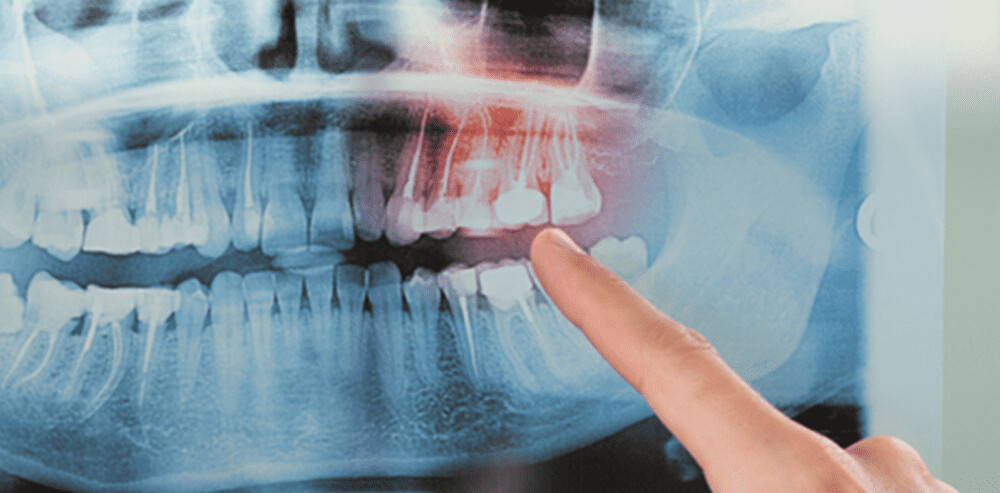

Impacted teeth and surgical extraction

An impacted tooth is one that has been blocked from emerging from the gums and is often discovered during a dental X-ray. Some impacted teeth will eventually break through the gums without treatment; also, removing baby teeth or orthodontic treatment can sometimes allow the teeth to come in properly. Other times, tooth extraction is necessary if the teeth are unable to erupt through the gums on their own. Often, surgical extraction is used on wisdom teeth or maxillary canines that cannot be guided to the correct position.